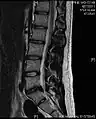

- Magnetic resonance imaging is the gold standard study for confirming a suspected LDH. With a diagnostic accuracy of 97%, it is the most sensitive study to visualize a herniated disc due to its significant ability in soft tissue visualization. MRI also has higher inter-observer reliability than other imaging modalities. It suggests disc herniation when it shows an increased T2-weighted signal at the posterior 10% of the disc. Degenerative disc diseases have shown a correlation with Modic type 1 changes. When evaluating for postoperative lumbar radiculopathies, the recommendation is that the MRI is performed with contrast unless otherwise contraindicated. MRI is more effective than CT in distinguishing inflammatory, malignant, or inflammatory etiologies of LDH. It is indicated relatively early in the course of evaluation (<8 weeks) when the patient presents with relative indications like significant pain, neurological motor deficits, and cauda equina syndrome. Diffusion tensor imaging is a type of MRI sequence used for detecting microstructural changes in the nerve root. It may be beneficial in understanding the changes that occur after herniated lumbar disc compresses a nerve root, and might help in differentiating the patients that need surgical intervention. In patients with a high suspicion of radiculopathy due to lumbar disc herniation, yet the MRI is equivocal or negative, nerve conduction studies are indicated.[44] T2-weighted images allow for clear visualization of protruded disc material in the spinal canal.

MRI scan of large herniation (on the right) of the disc between L4 and L5 vertebrae

A rather severe herniation of the L4–L5 disc